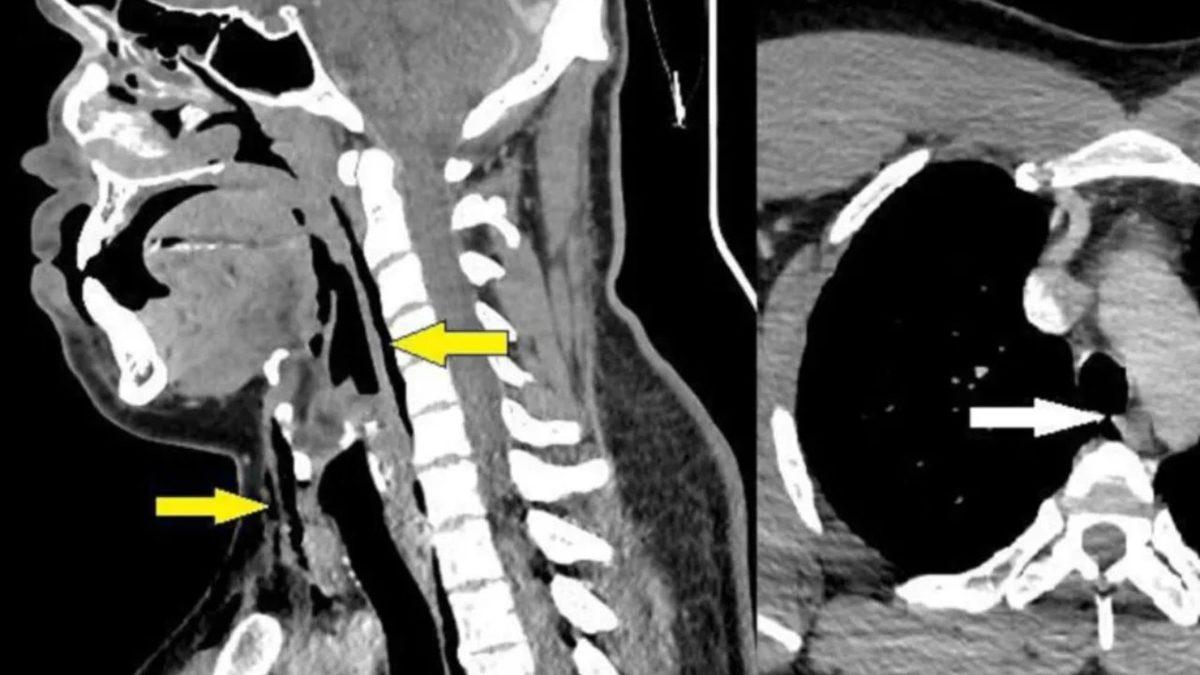

Acil servise vardığında, boynunda krepitus olarak bilinen bir çıtırtı sesi duyuluyordu ve röntgen, cerrahi amfizemi ortaya çıkardı. Cerrahi amfizem, cildin altına hava sızdıran travmatik bir yaralanmaydı.

Vakayı inceleyen doktorlar, kalbin havayla dolu bir dokuya çarptığında ortaya çıkabilen bir çıtırlı olan Hamman belirtisini tespit etti. Bunun üzerine bir tarama yapıldı ve adamın boynunun arkasını yırttığı anlaşıldı.